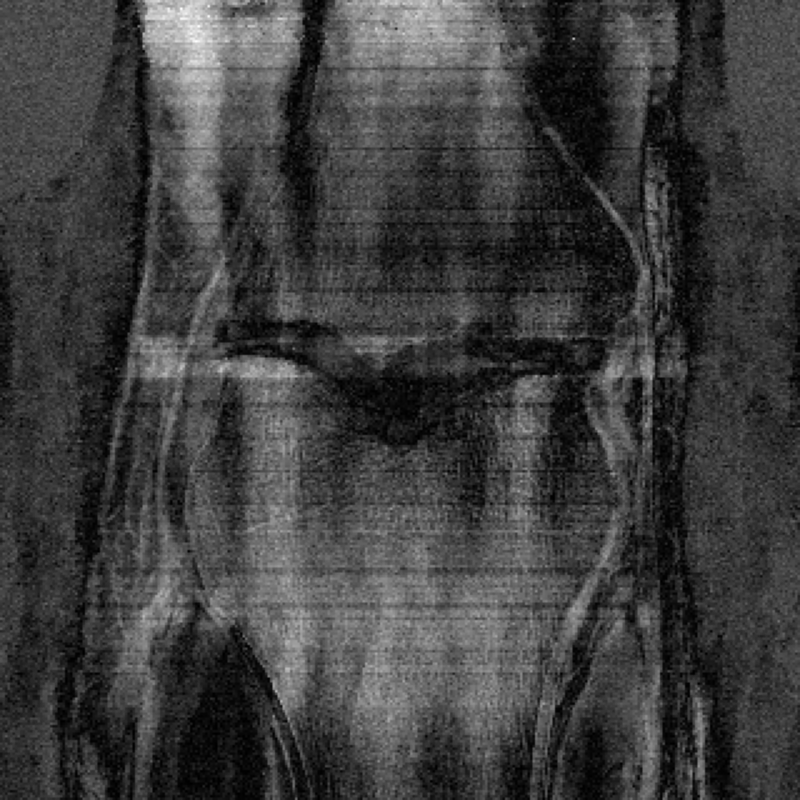

In Table 1 we present our main results. We present sample reconstructions for the deblurring problem and MRI reconstruction problem in Figs. 7 and 8. For reference, the ground truth, inputs to the networks, a total variation regularized reconstruction, and a RED reconstruction are presented in Figs. 5 and 6. We also provide in the Appendix a table of SSIM values as well as the full version of Table 1, which contains the standard deviations of PSNR.

While the magnitude of the improvements vary across domains and problems, we find that retraining the network with the proposed model adaptation techniques significantly improve performance by several dBs in the new setting. This effect is particularly striking in the case of MRI reconstruction with MoDL, where the βnaiveβ approach of replacing with in the network gives catastrophic results (a roughly 9 dB drop in reconstruction PSNR), while the proposed model adaptation approaches give reconstruction PSNRs within 1-2 dB of the baseline approach of training and testing with the same forward model in the case where is known.

Ground

IFFT

TV-Regularized

RED

Truth

Reconstruction